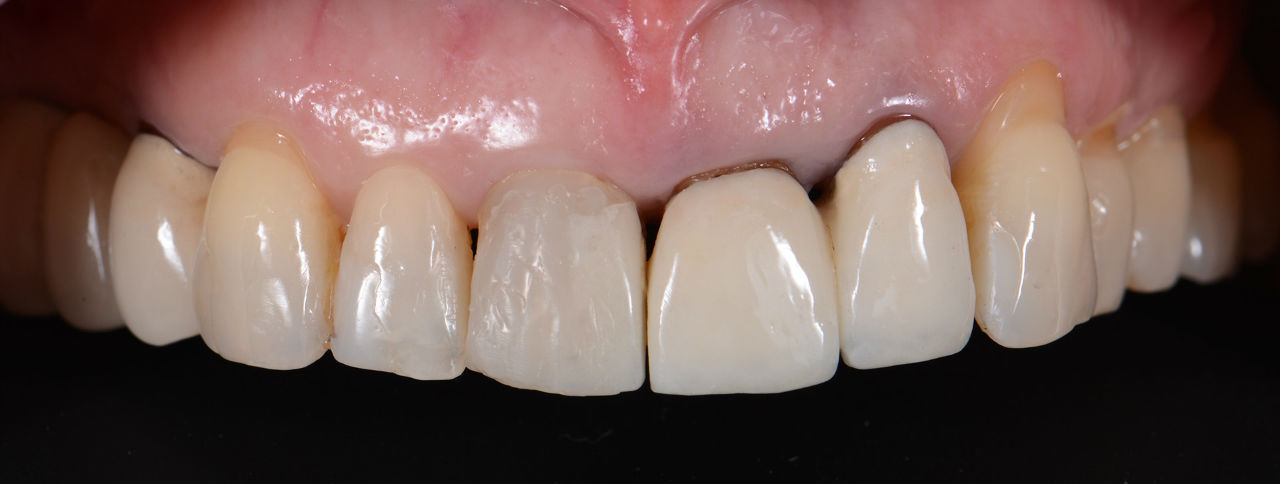

Случай 4: Дигитален дизайн на усмивката в Дента Консулт

Лечение без импланти